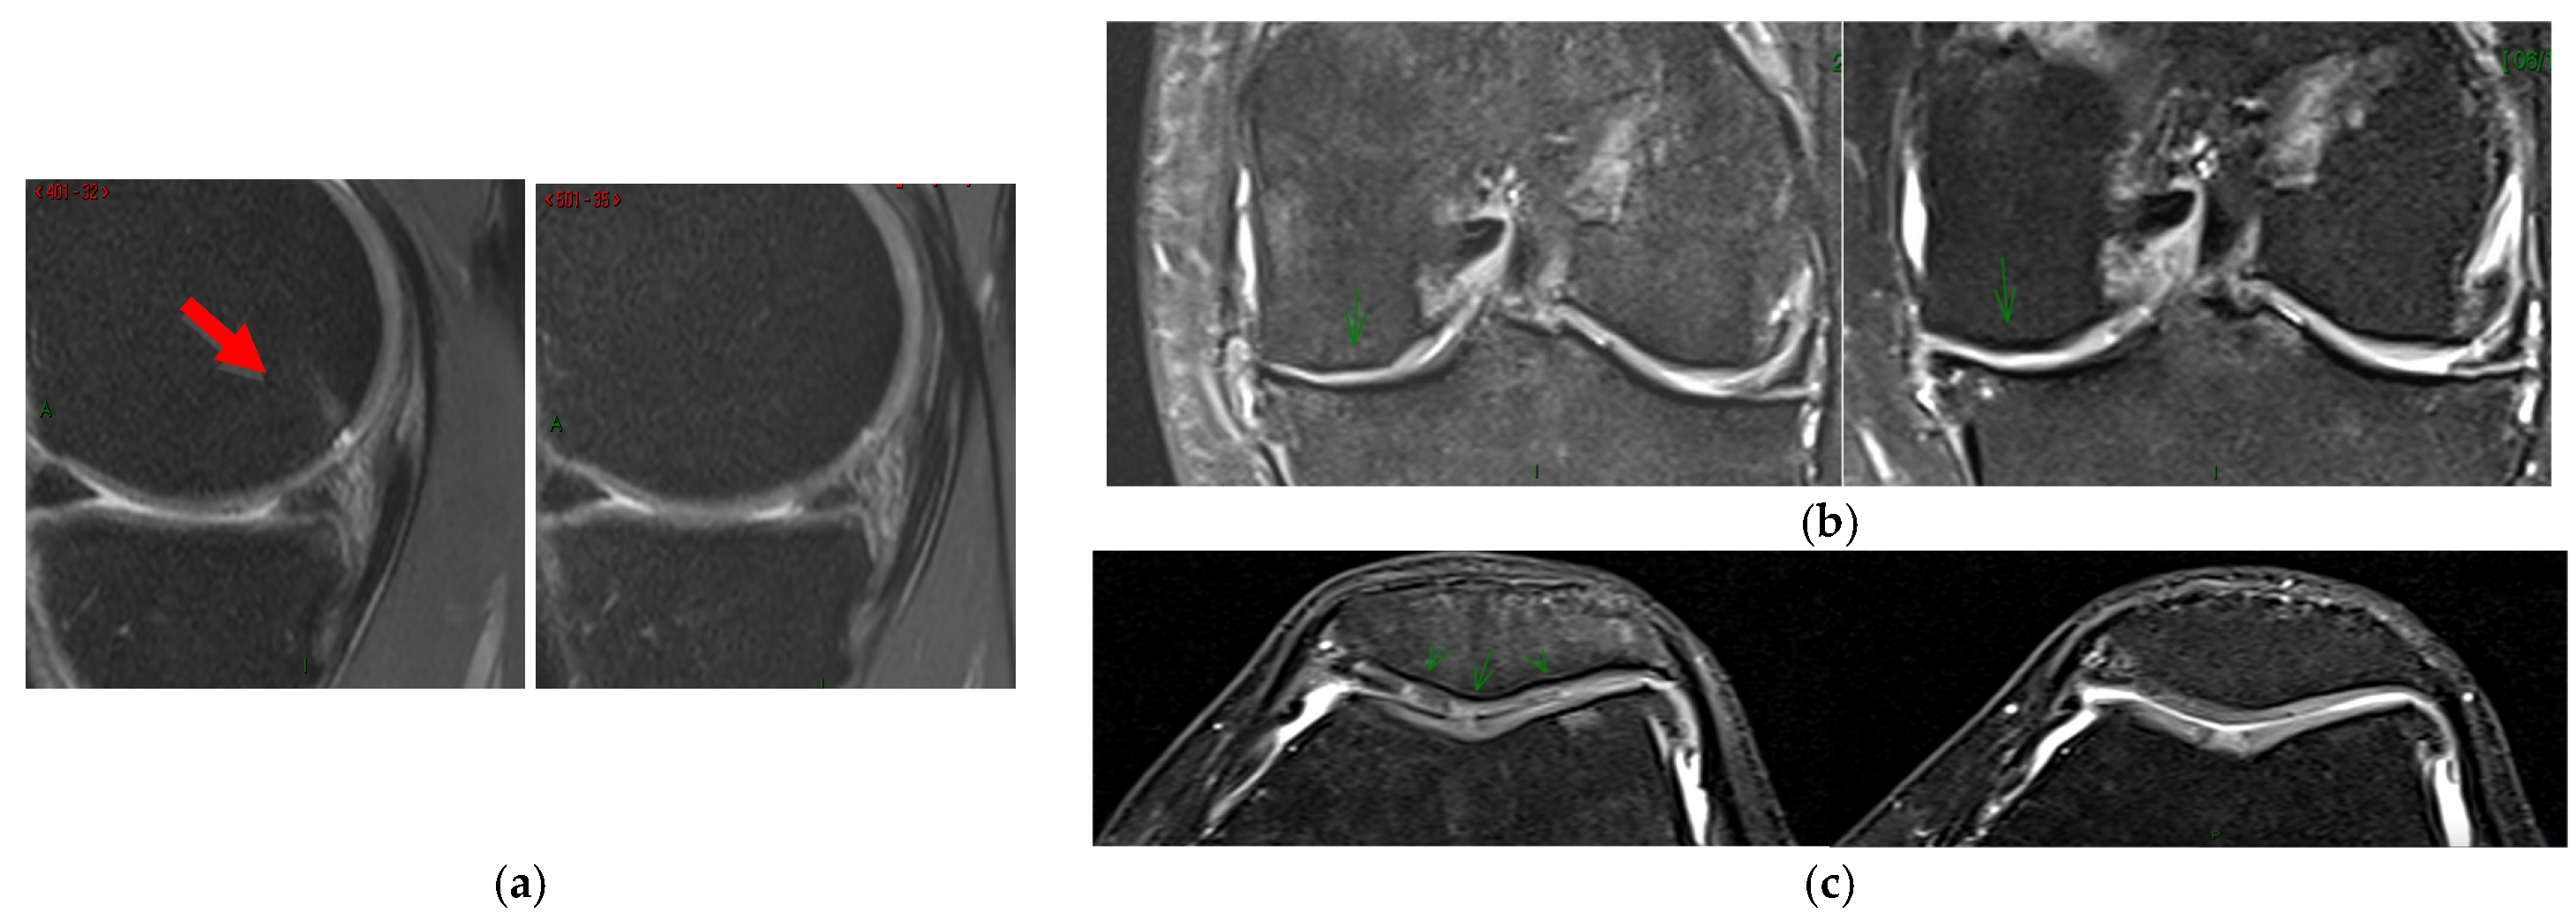

The potential relationship between clinical data and the change in the MOCART score was analyzed. The only notable association observed was between the cell yield contained in the SVF product and the total MOCART score, indicating a potentially relevant positive association (p = 0.032). A higher MSC percentage was associated with a greater positive change in the total MOCART score. Additionally, radiological improvements were noted in the MRI scans of several patients (see examples in Figure 3).

Structural changes in the knee joint have been sought after over the years. Although SVF has emerged as a potential treatment for cartilage regeneration because of its in vitro effects, evaluating anatomical changes using validated scores has been rarely undertaken [19]. In spite of the insufficient statistical power of our study, a weak yet potentially relevant positive correlation between the percentage of MSCs and improvement in the MOCART classification should be highlighted. Higher percentages of MSCs were associated with a more significant positive change in the MOCART total score. Song et al. [41] reported similar findings after three ADSC infiltrations over 96 weeks. Our results also suggest a similar trend with a single infiltration, indicating a potentially greater regenerative capacity of SVF products than that of purely expanded MSCs. While Muthu et al. [42] observed superior functional outcomes with non-cultivated MSCs for KOA compared with cultivated MSCs, the debate continues with compelling arguments supporting both cultivated and non-cultivated products. More extensive studies with larger patient populations are needed to establish clear associations and provide more precise guidance on treatment indications, types, and timing, thereby enhancing therapeutic efficacy and regenerative potential.

Figure 3. MRI images pre- (left) and post-treatment (right). (a) A decreased signal intensity and surface extension in subchondral bone were found (red arrow). (b,c) An increased cartilage thickness was found in the medial tibiofemoral joint and in the patellofemoral joint, respectively (green arrows).